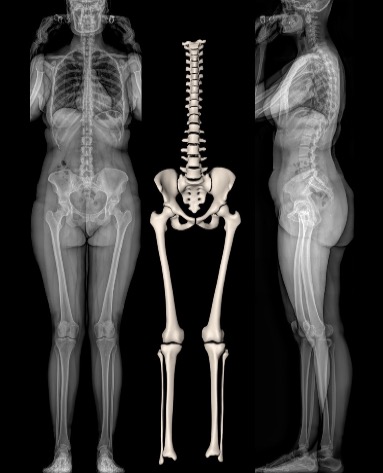

Ce système permet la réalisation de radiographies du corps entier en position debout, en une seule acquisition, sans assemblage d’images et sans distorsion verticale. Des clichés numériques de face et de profil, de tout ou partie du corps, sont obtenus simultanément avec une qualité d’image exceptionnelle et sans aucun agrandissement, garantissant une fiabilité parfaite des mesures.

À la manière d’une photocopieuse, un très fin faisceau de rayons X balaye le corps du patient de la tête aux pieds, réalisant une image de face et une de profil en quelques secondes et de manière simultanée. L’extrême sensibilité des détecteurs développés par Georges Charpak permet cette acquisition corps entier avec une dose de radiation 9 fois inférieure à celle des méthodes radiologiques classiques et jusqu’à 100 fois inférieure à celle d’un scanner.